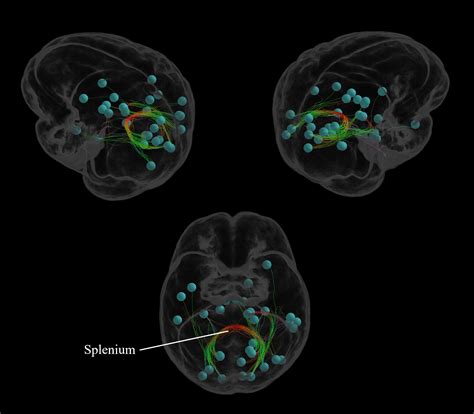

Modern neuroscience is increasingly focused on "connectomics"—the comprehensive mapping of neural connections in the brain. The splenium of corpus callosum is a central component in these connectome maps. By using techniques like Diffusion Tensor Imaging (DTI), researchers can visualize the direction and integrity of the fibers within the splenium with unprecedented clarity. This technology allows scientists to see how different brain regions are "wired" together and how these wires change in response to learning, aging, and disease.

As research progresses, we are finding that the splenium is not just a passive bridge but a dynamic participant in brain health. Some studies suggest that training the brain through meditation or complex motor tasks can actually enhance the structural integrity of callosal fibers. This suggests a degree of neuroplasticity that was previously thought to be impossible in deep white matter structures. The prospect of using targeted interventions to improve callosal connectivity offers exciting potential for treating cognitive decline and neurodevelopmental disorders.

The fibers passing through the splenium are predominantly responsible for connecting the temporal, parietal, and occipital lobes. This anatomical arrangement is crucial because these lobes are heavily involved in sensory perception. By facilitating communication between these areas, the splenium ensures that visual input—processed primarily in the occipital lobes—is integrated seamlessly with auditory information and complex sensory data from the parietal lobes.